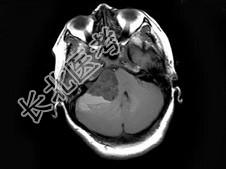

- 单项选择题女,37岁, 右耳听力下降半年,走路不稳2周, MRI检查如图,最可能的诊断为 ( )

A、听神经瘤

B、三叉神经瘤

C、胆脂瘤

D、小脑胶质瘤

E、未见异常